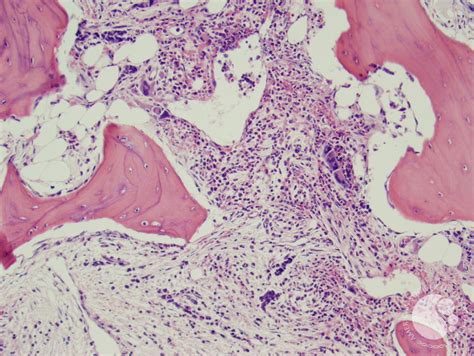

Post-polycythemic myelofibrosis, bone marrow core 1 from imagebank.hematology.org What is a bone marrow transplant? The patient is an 11 years old child with a mediastinal tumor. The marrow aspirate shows an invasion with neuroblastoma cells and characteristic images of neuropile threads. The bone marrow donor programme (bmdp) manages singapore's only register of volunteer bone marrow donors. Bone marrow edema is commonly seen with fractures and other serious bone or joint injuries, especially those involving the spine, hip, knees, or ankle. More than 35,000 people have donated bone marrow to a stranger without a single. World marrow donor association matching donors • serving patients since 1994. This image belongs to set:

Neuroblastoma with bone marrow invasion. Bone marrow donation requires less than five percent of marrow cells. The national marrow donor program® (nmdp) has formal business relationships with donor registries in other countries. Bone marrow edema is commonly seen with fractures and other serious bone or joint injuries, especially those involving the spine, hip, knees, or ankle. Bone marrow stem cells are collected from the posterior section of the pelvic bone under general anesthesia. Everything we do is for the goal of finding a donor for every patient. World marrow donor association matching donors • serving patients since 1994. The nbmtlink has been linking, curing, and caring since 1992, providing a number of services and resources. After the surgery, you might feel tired or weak and have trouble walking for a few days. A challenge for a future bm banking system will be to manage the prolonged ischemia times that are inevitable when bones procured at. I had a bone marrow aspiration completed for a stem cell banking process about 3.5 months ago now, and i'm still having pain as if it was done yesterday. The national bone marrow transplant link is dedicated to helping individuals and their families from diagnosis through survivorship. We work with hospitals, cancer centers, and other organizations to reinforce and complement medical care.